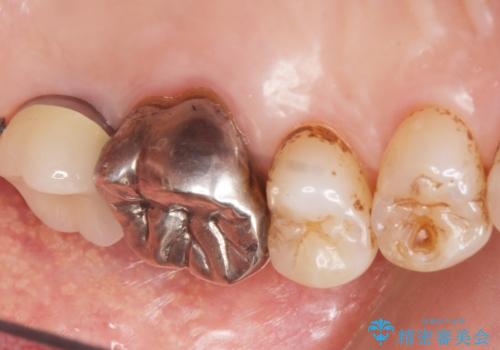

奥歯(左上7)のメタルインレー(銀の詰め物)を除去し精査したところ、奥歯はわれていました。

根尖近くまで深くヒビが入っており保存不可能な状態でした。

患者様のご希望により抜歯してインプラントによる治療を行いました。